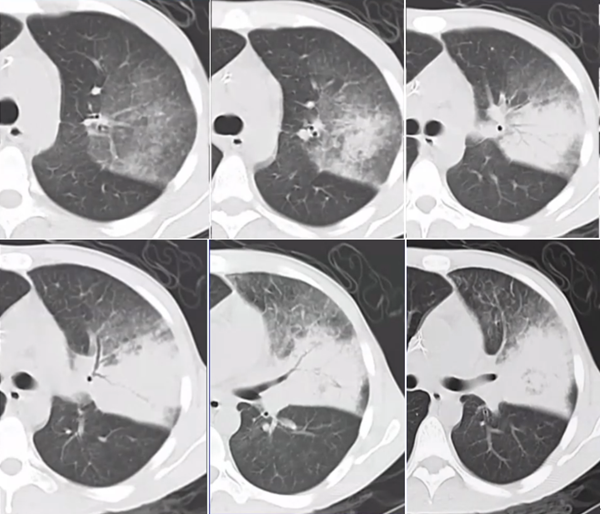

抗感染治疗后病变仍持续进展,斑片状渗出灶范围扩大,并出现实变影,纵隔窗可见密度不均匀,其中分布点状低密度灶(图3)

图片

图3  患者胸部CT(2014-07-26)

即使采取了广泛覆盖革兰氏阴性菌和阳性菌的多药联合的抗感染治疗策略,病变仍然不断进展,周围晕征不断扩大,实变成分增加,内见低密度影(图4)

图4  患者胸部CT(2014-07-31)